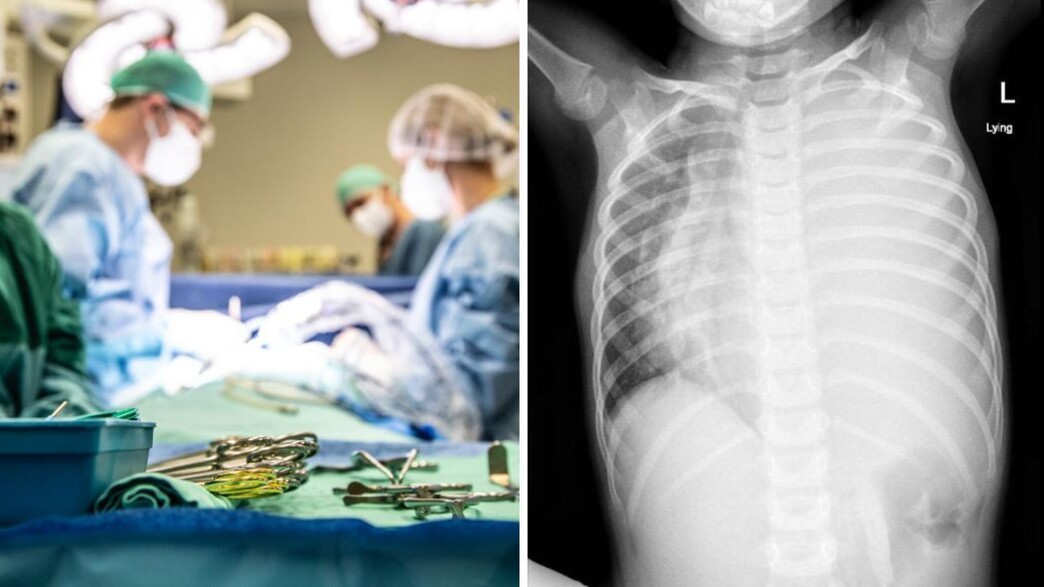

בת 4 עם גידול נדיר | צילום: איכילוב

בצילום חזה הודגמה הצללה כמעט מלאה של בית החזה השמאלי. היא נשלחה בדחיפות לבדיקת CT  חזה דחופה ובה התגלה תהליך גידולי ענק, שמילא כמעט את כל הריאה השמאלית.

לפני ואחרי הטיפול

הגידול שנצפה לפני הטיפול הכימי (ימין) ואחריו (שמאל | צילום: איכילוב